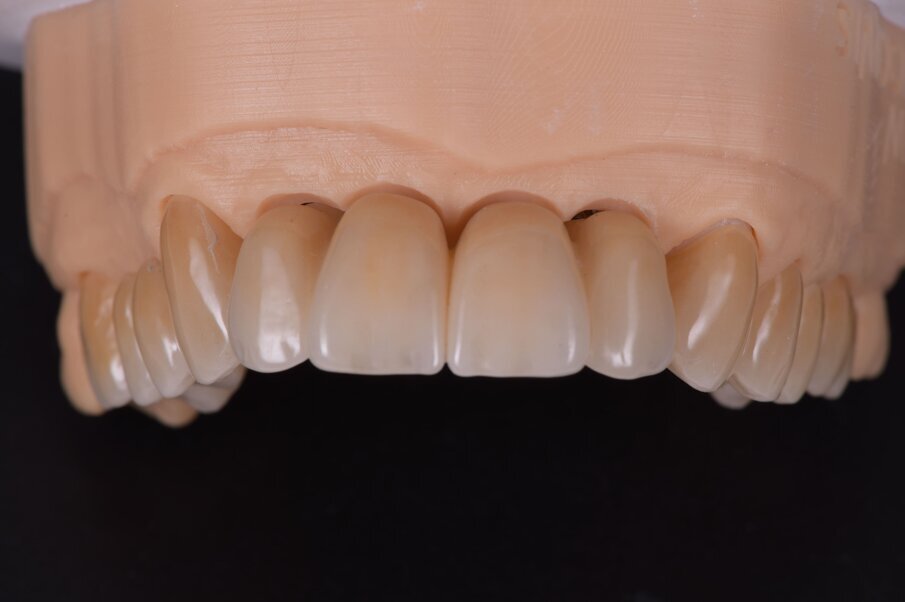

I dati raccolti sono molti ma la procedura digitale consente di sommarli e confrontarli senza limiti e indicando le possibili migliori e correzioni lungo il percorso. Dopo un breve periodo di condizionamento dei tessuti (Fig. 30) rileviamo l’impronta master per la finalizzazione ultima della riabilitazione protesica. L’impronta degli elementi naturali viene rilevata posizionando dei fili detrattori secondo la tecnica del doppio filo mentre per gli impianti verranno usati gli scan body dedicati (Fig. 31). Le potenzialità digitali consentiranno di avere una stabile lettura della posizione di centrica rilevandola prima della rimozione dei provvisori e sovrapponendola a provvisori rimossi (Fig. 32). In laboratorio l’odontotecnico realizza i modelli (Figg. 33, 34) sovrappone le immagini (Fig. 35) e raccoglie gli elaborati dei vari passaggi che porteranno alla finalizzazione del progetto digitale (Figg. 36, 37). Gli impianti in Zirconia non offrono molte soluzioni protesiche, è importante che il loro posizionamento tenga conto di quest’aspetto mettendo l’odontotecnico nelle condizioni più favorevoli (Fig. 38). Questa sistematica prevede l’uso di un moncone in titanio cementato nella struttura protesica che permette l’avvitamento all’interno dell’impianto. Nella connessione implantare è presente un’intercapedine dove alloggia il collarino in titanio del T-base totalmente inglobato all’interno della zirconia, evitando comunicazioni coi tessuti adiacenti. Va comunque considerato l’aspetto tecnico importante legato allo spessore della struttura in zirconia che deve avvolgere l’intero moncone in titanio. (Fig. 39, 40).

Fig. 35_Sovrapposizione di un’immagine stilizzata degli elementi realizzabili con un margine muso ricreato.

Fig. 36_Wax-up digitale funzionalizzato per entrambe le arcate in visione frontale.

Fig. 37_La medesima immagine viene sottratta dagli elementi di supporto. Tale visione consente di evidenziare i margini coronali, di valutare i movimenti masticatori, gli svincoli coronali le conformazioni anatomiche ottimizzando le singole funzioni.